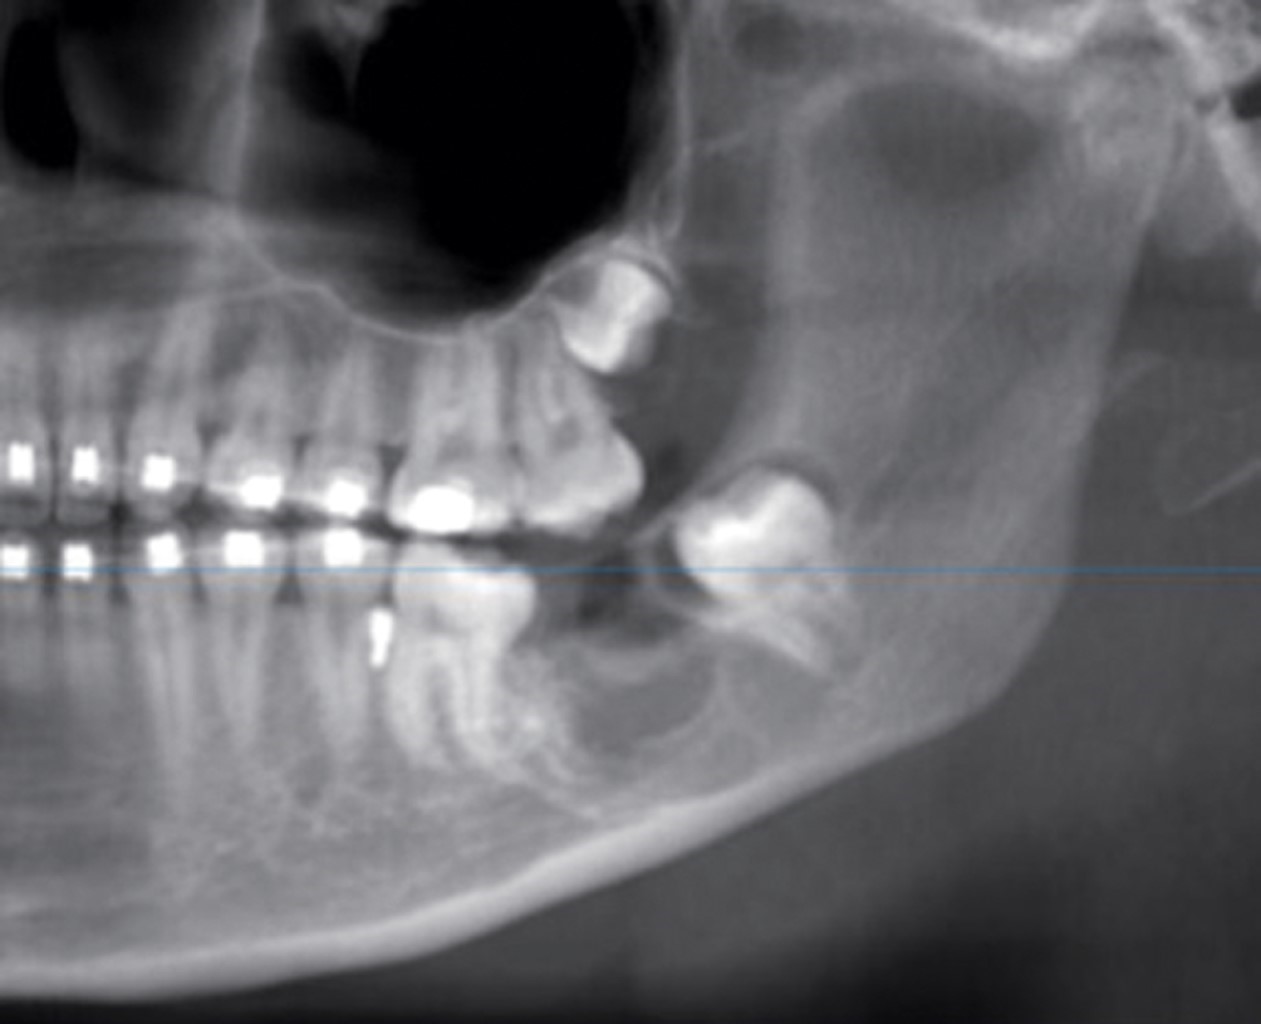

La radiografía panorámica permitió observar un área radiolúcida unilocular que se extendía a partir del cuerpo mandibular (Figura 1), desde la zona distal del primer molar inferior izquierdo hasta la parte mesial del segundo molar incluido, involucrando el canal del nervio inferior. El segundo molar inferior estaba incluido en la lesión y desplazado posterosuperiormente, así como desplazamiento basal del conducto dentario inferior. En la tomografía axial computarizada con reconstrucción se apreció una masa isodensa en el cuerpo y rama mandibular izquierda, con expansión de corticales vestibular y lingual (Figura 2).